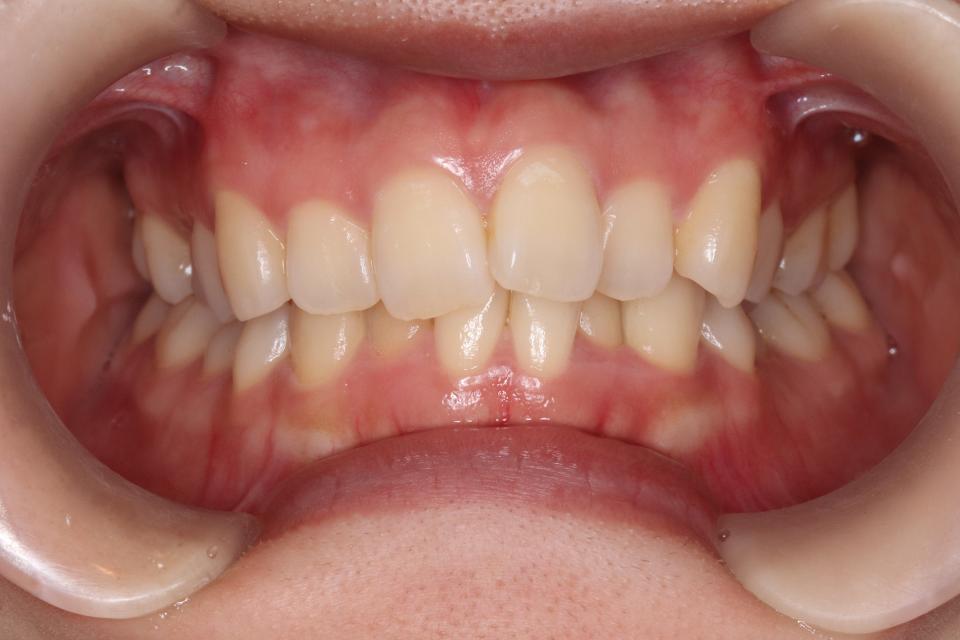

上顎前突(出っ歯)のマウスピース矯正治療例(抜歯あり)

矯正治療前

20代女性の患者さんです。

歯並びのガタガタと出っ歯気になり矯正治療を始めました。